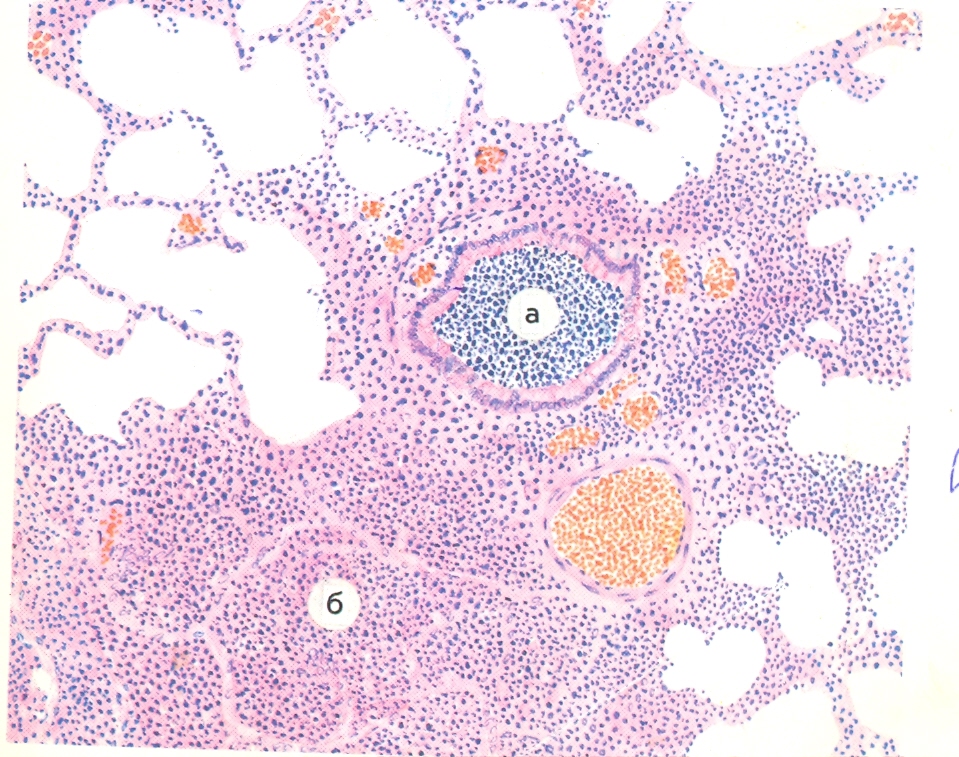

Микроскопический взгляд на мишитарный туберкулез легкого: фотодокументация